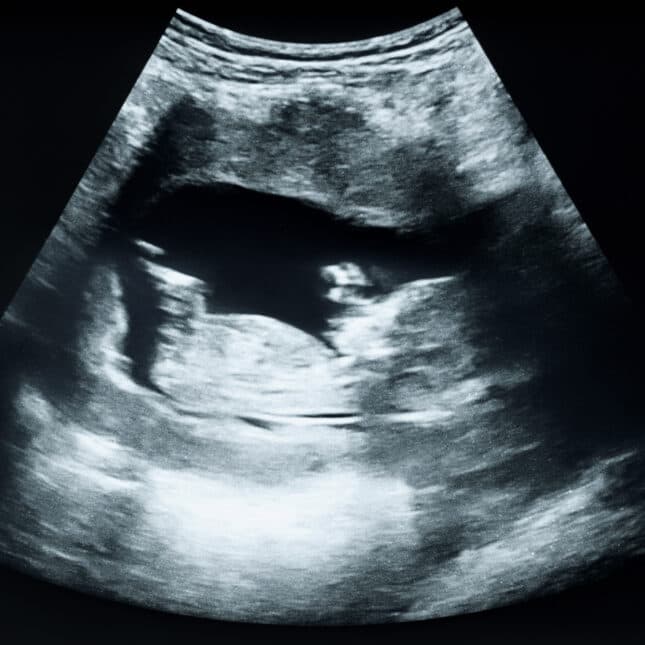

C-section rate in 2025 highest in a decade — txtfeed